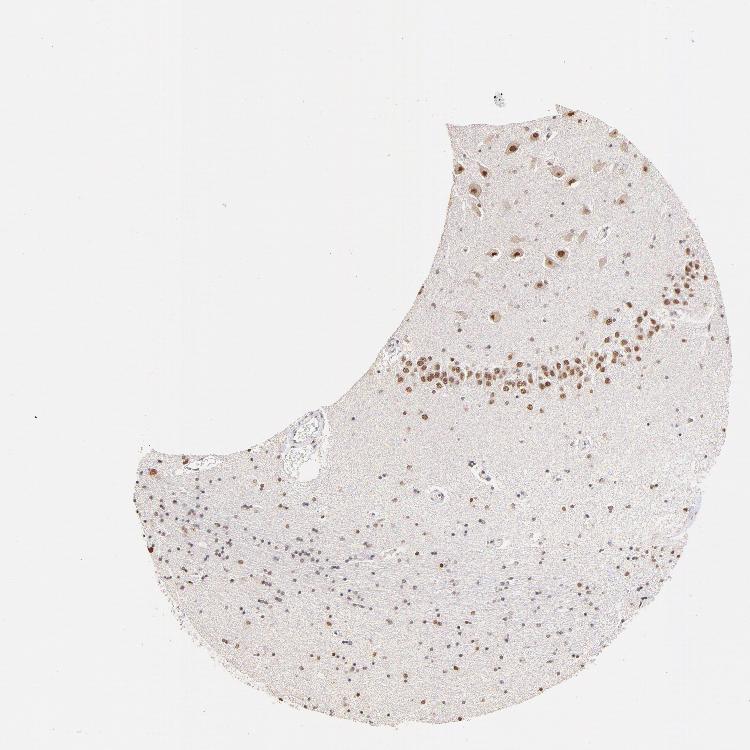

HIPPOCAMPUS - Antibody stainingi

Antibody staining in the annotated cell types in the current human tissue is reported as not detected, low, medium, or high, based on conventional immunohistochemistry profiling in selected tissues. This score is based on the combination of the staining intensity and fraction of stained cells.

Each image is clickable and will lead to virtual microscopy that enables deeper exploration of all samples and also displays staining intensity scores, fraction scores and subcellular localization as well as patient and tissue information for each sample.

Antibody HPA003142

Glial cells Medium

Neuronal cells Medium